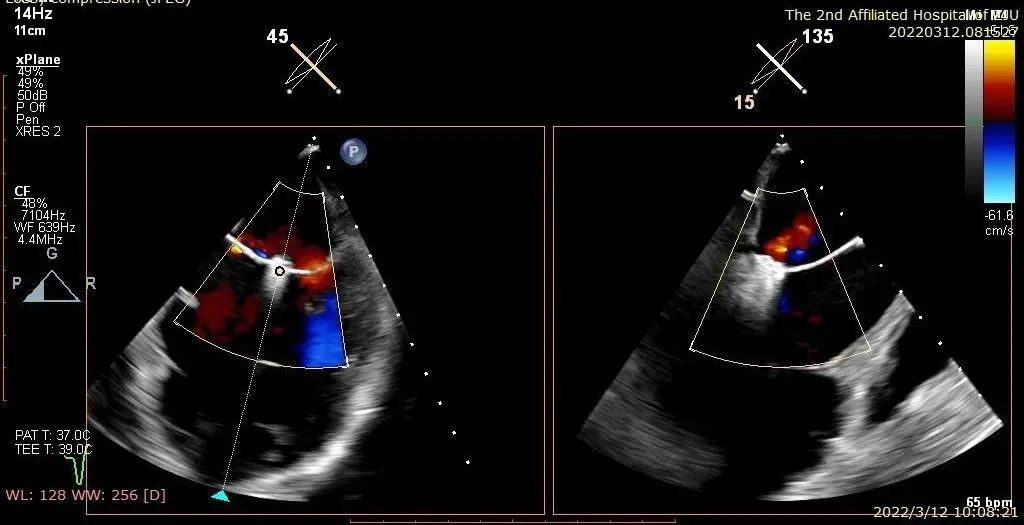

患者二术前二尖瓣反流4+